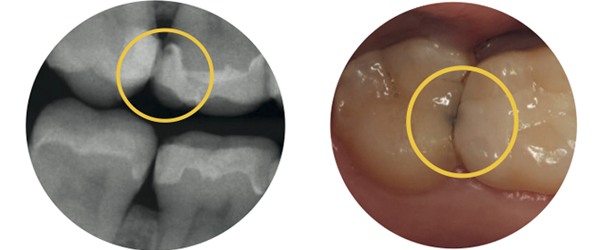

인레이 하방에 세균이 들어가서 2차충치가 생긴 모습입니다. 이런 경우 인레이 안쪽의 치아가 썩게 되어 더 큰 문제를 유발할 수 있습니다 (출처: https://www.dentaltix.com/)

하지만 실제로 더 흔한 문제는

인레이 가장자리에서 생기는 2차 충치입니다.

아무리 튼튼한 인레이라도

경계부가 마모되거나

틈이 생기면

그 아래로 세균이 들어가요 😥